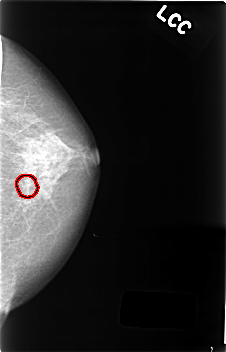

C_0406_1.LEFT_CC

LEFT_CC LINES 4576 PIXELS_PER_LINE 2928 BITS_PER_PIXEL 12 RESOLUTION 50 OVERLAY

FILE: C_0406_1.LEFT_CC.OVERLAY

TOTAL_ABNORMALITIES 1

ABNORMALITY 1

LESION_TYPE CALCIFICATION TYPE AMORPHOUS DISTRIBUTION CLUSTERED

ASSESSMENT 4

SUBTLETY 2

PATHOLOGY BENIGN

TOTAL_OUTLINES 1

BOUNDARY